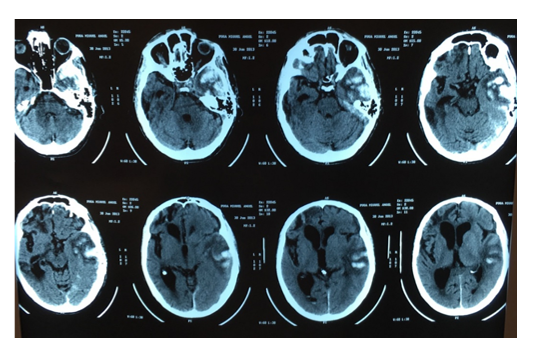

Despite of EEG normalization, clinical status did not improve. Lumbar puncture was normal, Brain CT and MRI showed old ischemic and hemorrhagic sequelae. After 2 weeks mental status was below his previous baseline, hyperactive and hypoactive delirium persisted despite antipsychotic medication. A new contrast-MRI showed right frontal pachymeningeal, leptomeningeal enhancement, and gyral edema in FLAIR/T2 sequences, the same was retrospectively observed in the first non-contrasted MRI (Image 2). Despite atypical neuroimaging and age, inflammatory amyloid angiopathy was suspected due to meningeal enhancement, new seizures onset and continuous cognitive deterioration during the months before hospitalization. As a differential diagnosis post seizures edema was proposed, but none DWI restriction was observed in the first and second MRI within 2 weeks. Finally, 3 g of methylprednisolone was administered followed by oral prednisone. A slight improvement was observed (the patient recovered from prostration and start walking again, but persisted markedly confused). 3 months later the patient died from pneumonia.